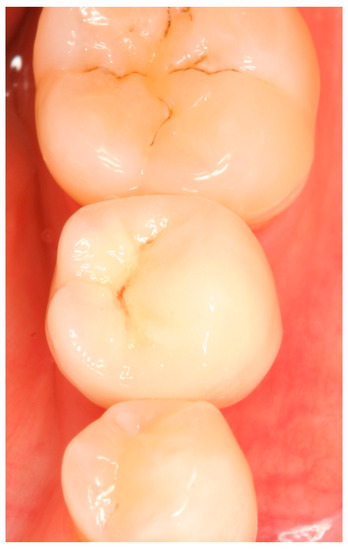

Appendix B. Exemplary Photographs and Radiographs from a Patient at Different Examination Time Points and a More Negative Outcome

Patient B:

Figure A22.

Clinical situation at the 5-year follow-up. Occlusal view.